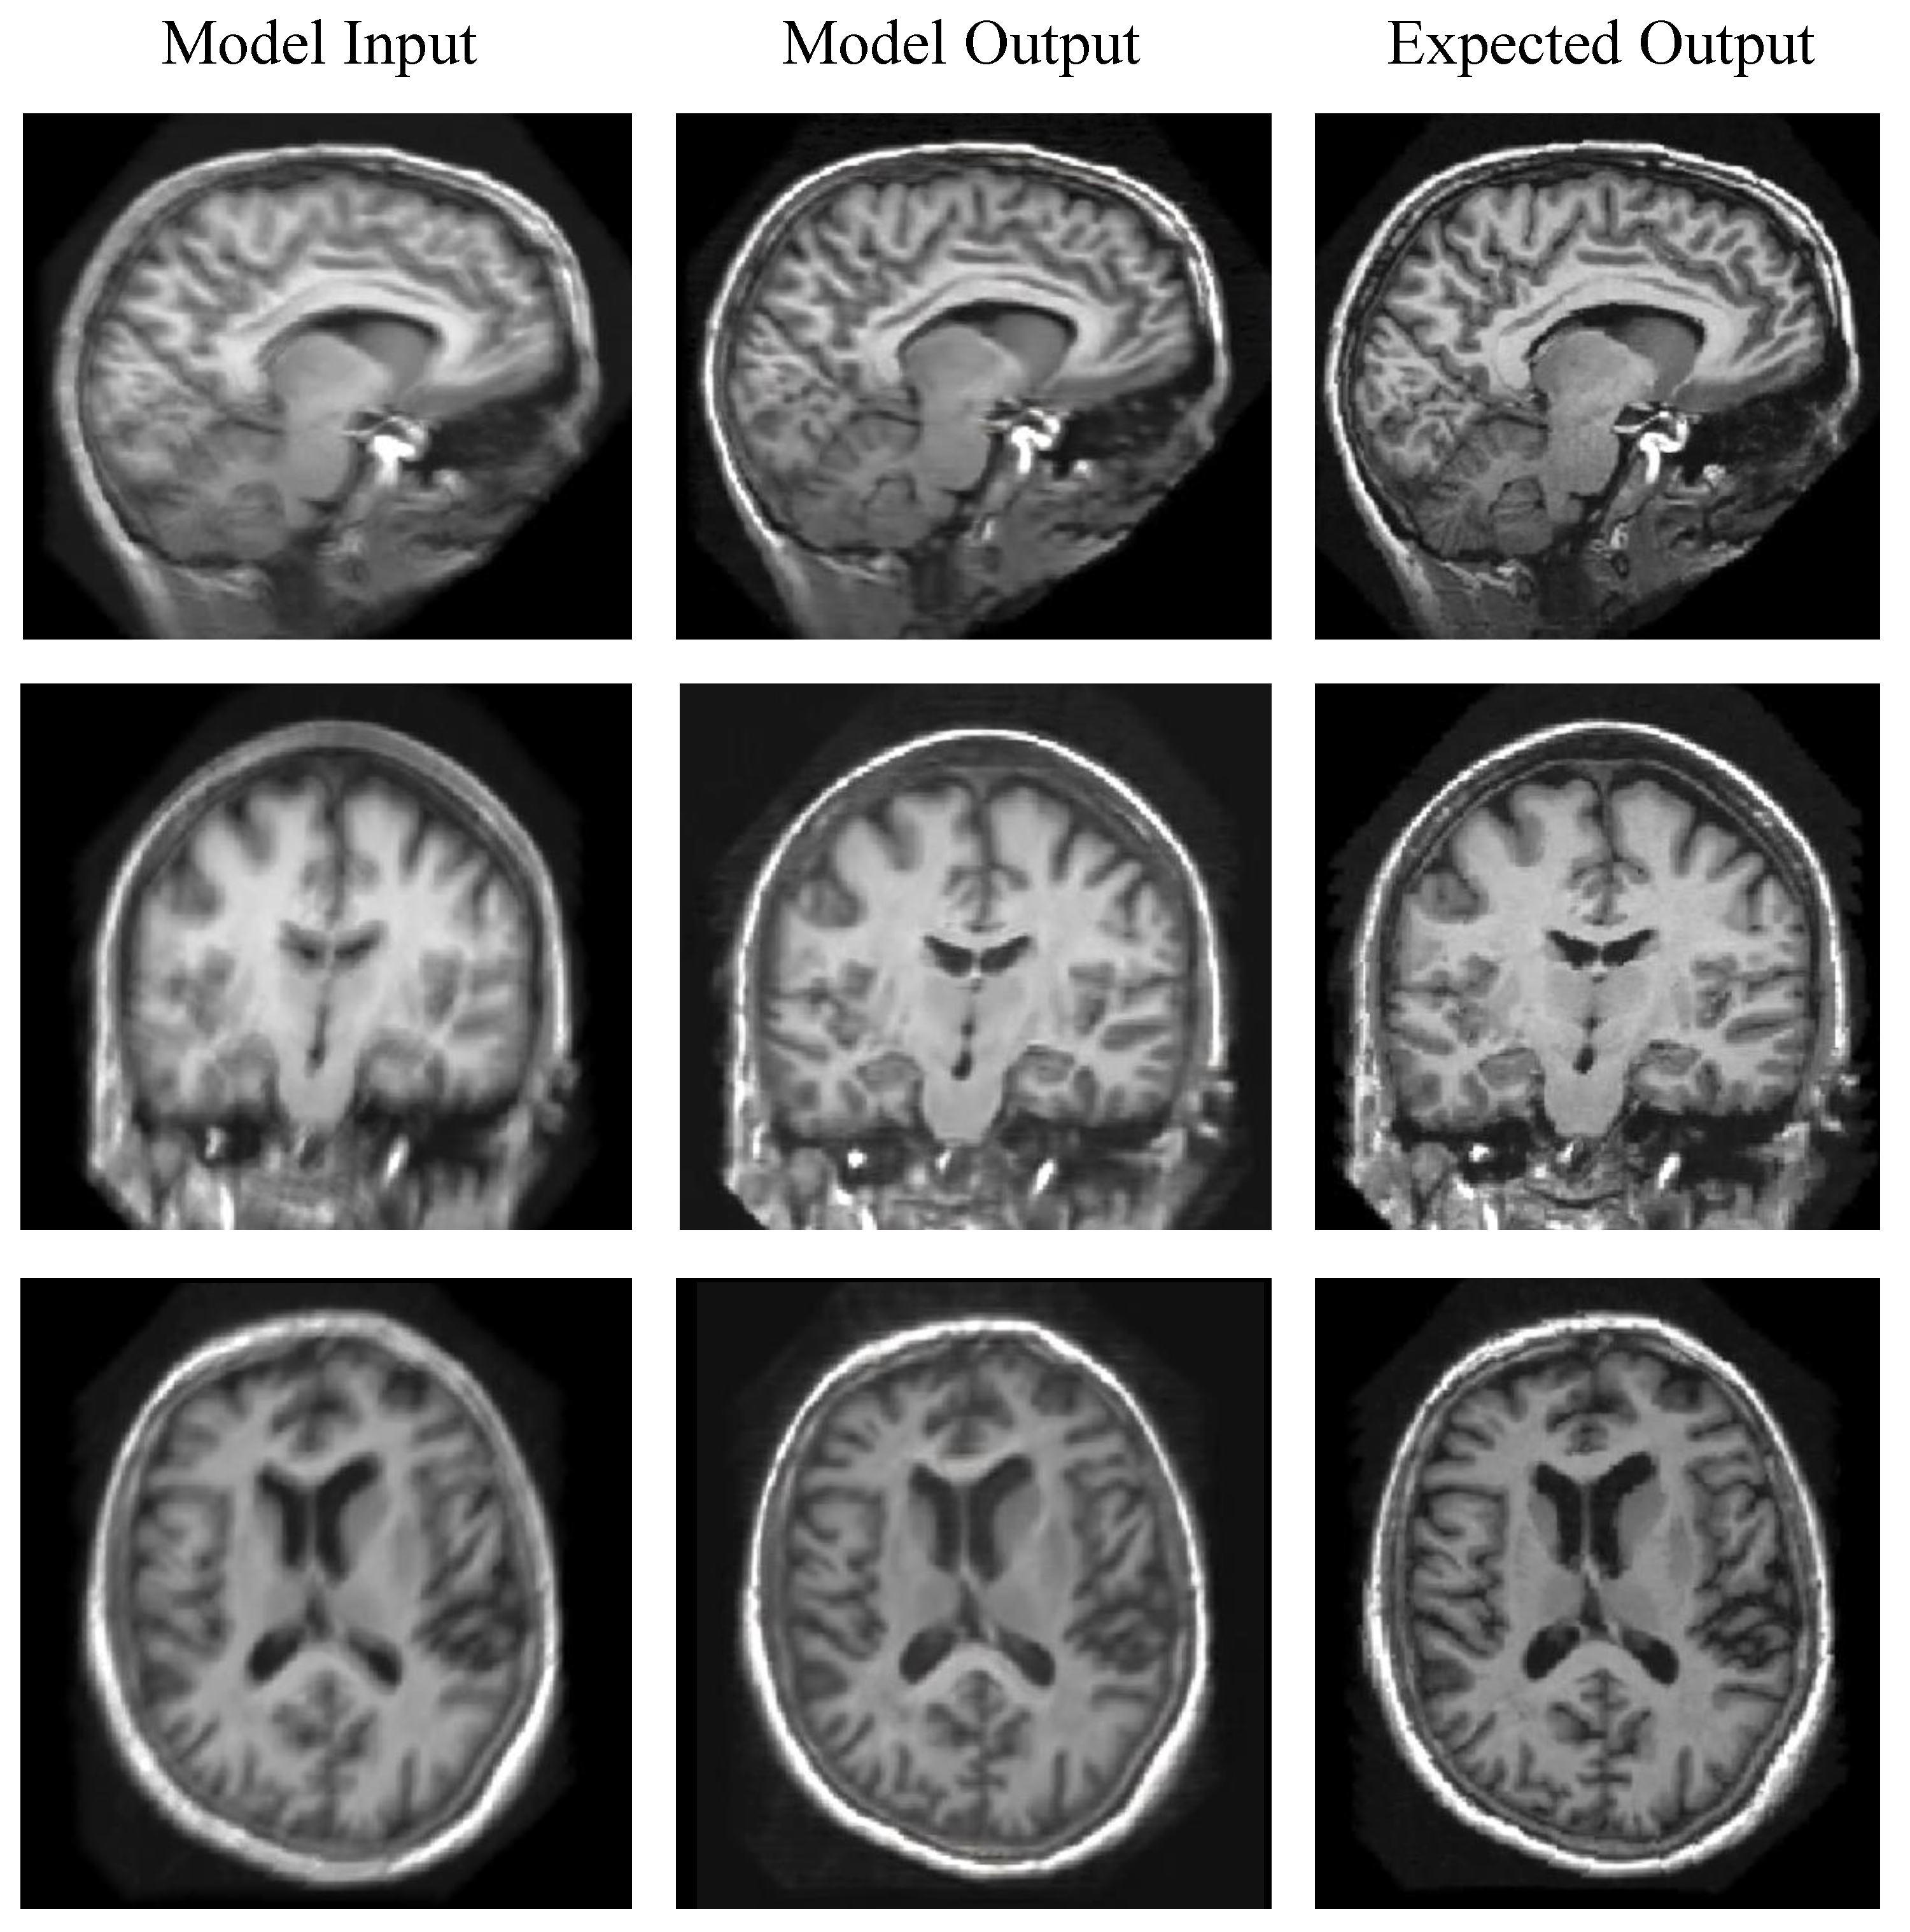

Evaluation on Synthetic Images

5.3. Evaluation on Real-World Scans